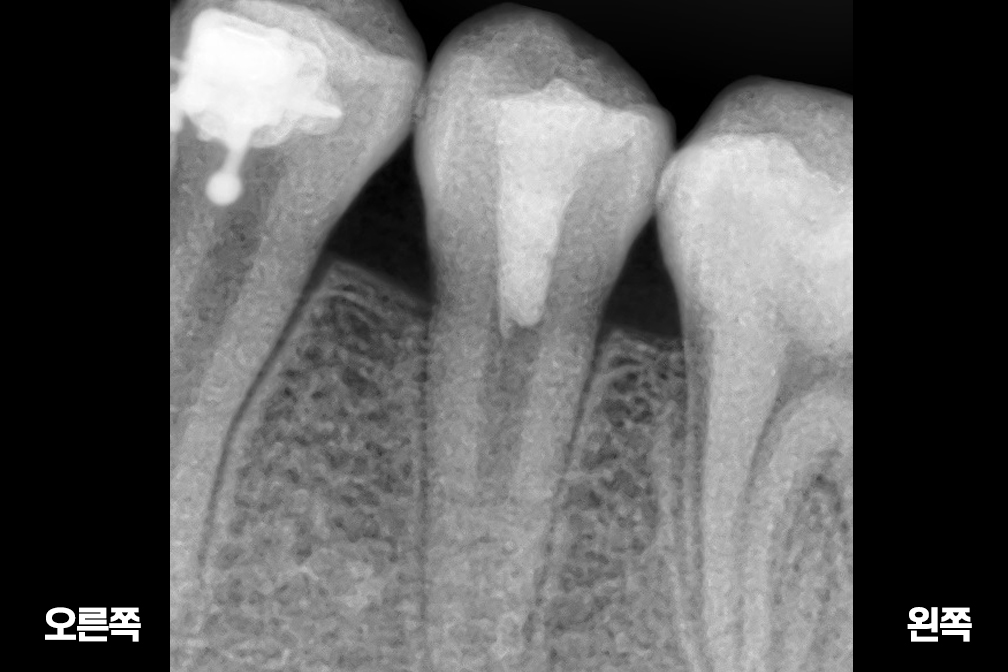

Before 2025년 6월 25일